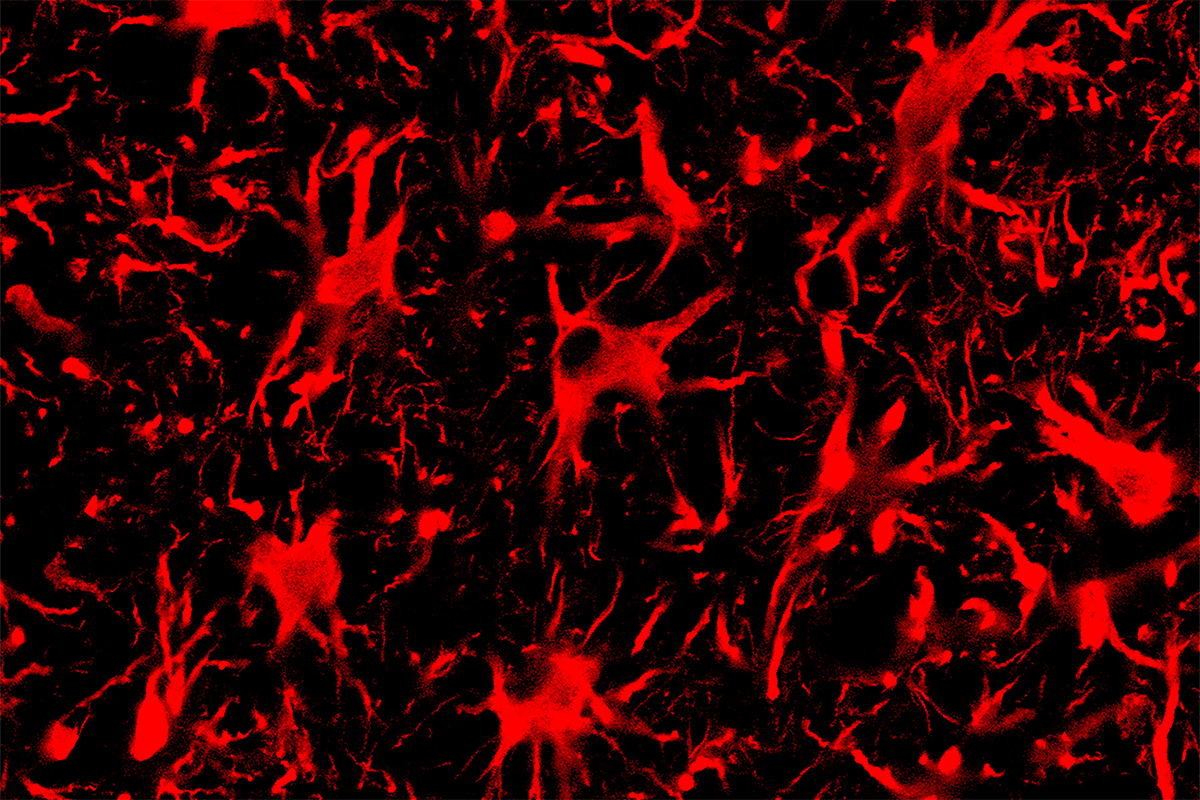

Spinal cord astrocytes, the cells seen in this fluorescent microscope image, are involved in the progression of ALS. A new CRISPR-Cas13 system targeting mutant protein production in these cells improved outcomes for mice with ALS.

Rather than the popular DNA-editing CRISPR-Cas9 technique, the new approach uses CRISPR-Cas13, which can target mRNA – the messenger molecule that carries protein blueprints transcribed from DNA. The Illinois team developed Cas13 systems to target and cut RNAs that code for mutant proteins that trigger ALS and Huntington’s disease, effectively silencing the mutant genes without disturbing the cell’s DNA, said study leader Thomas Gaj (BSD), an Illinois professor of bioengineering. The team published its results in the journal Science Advances.